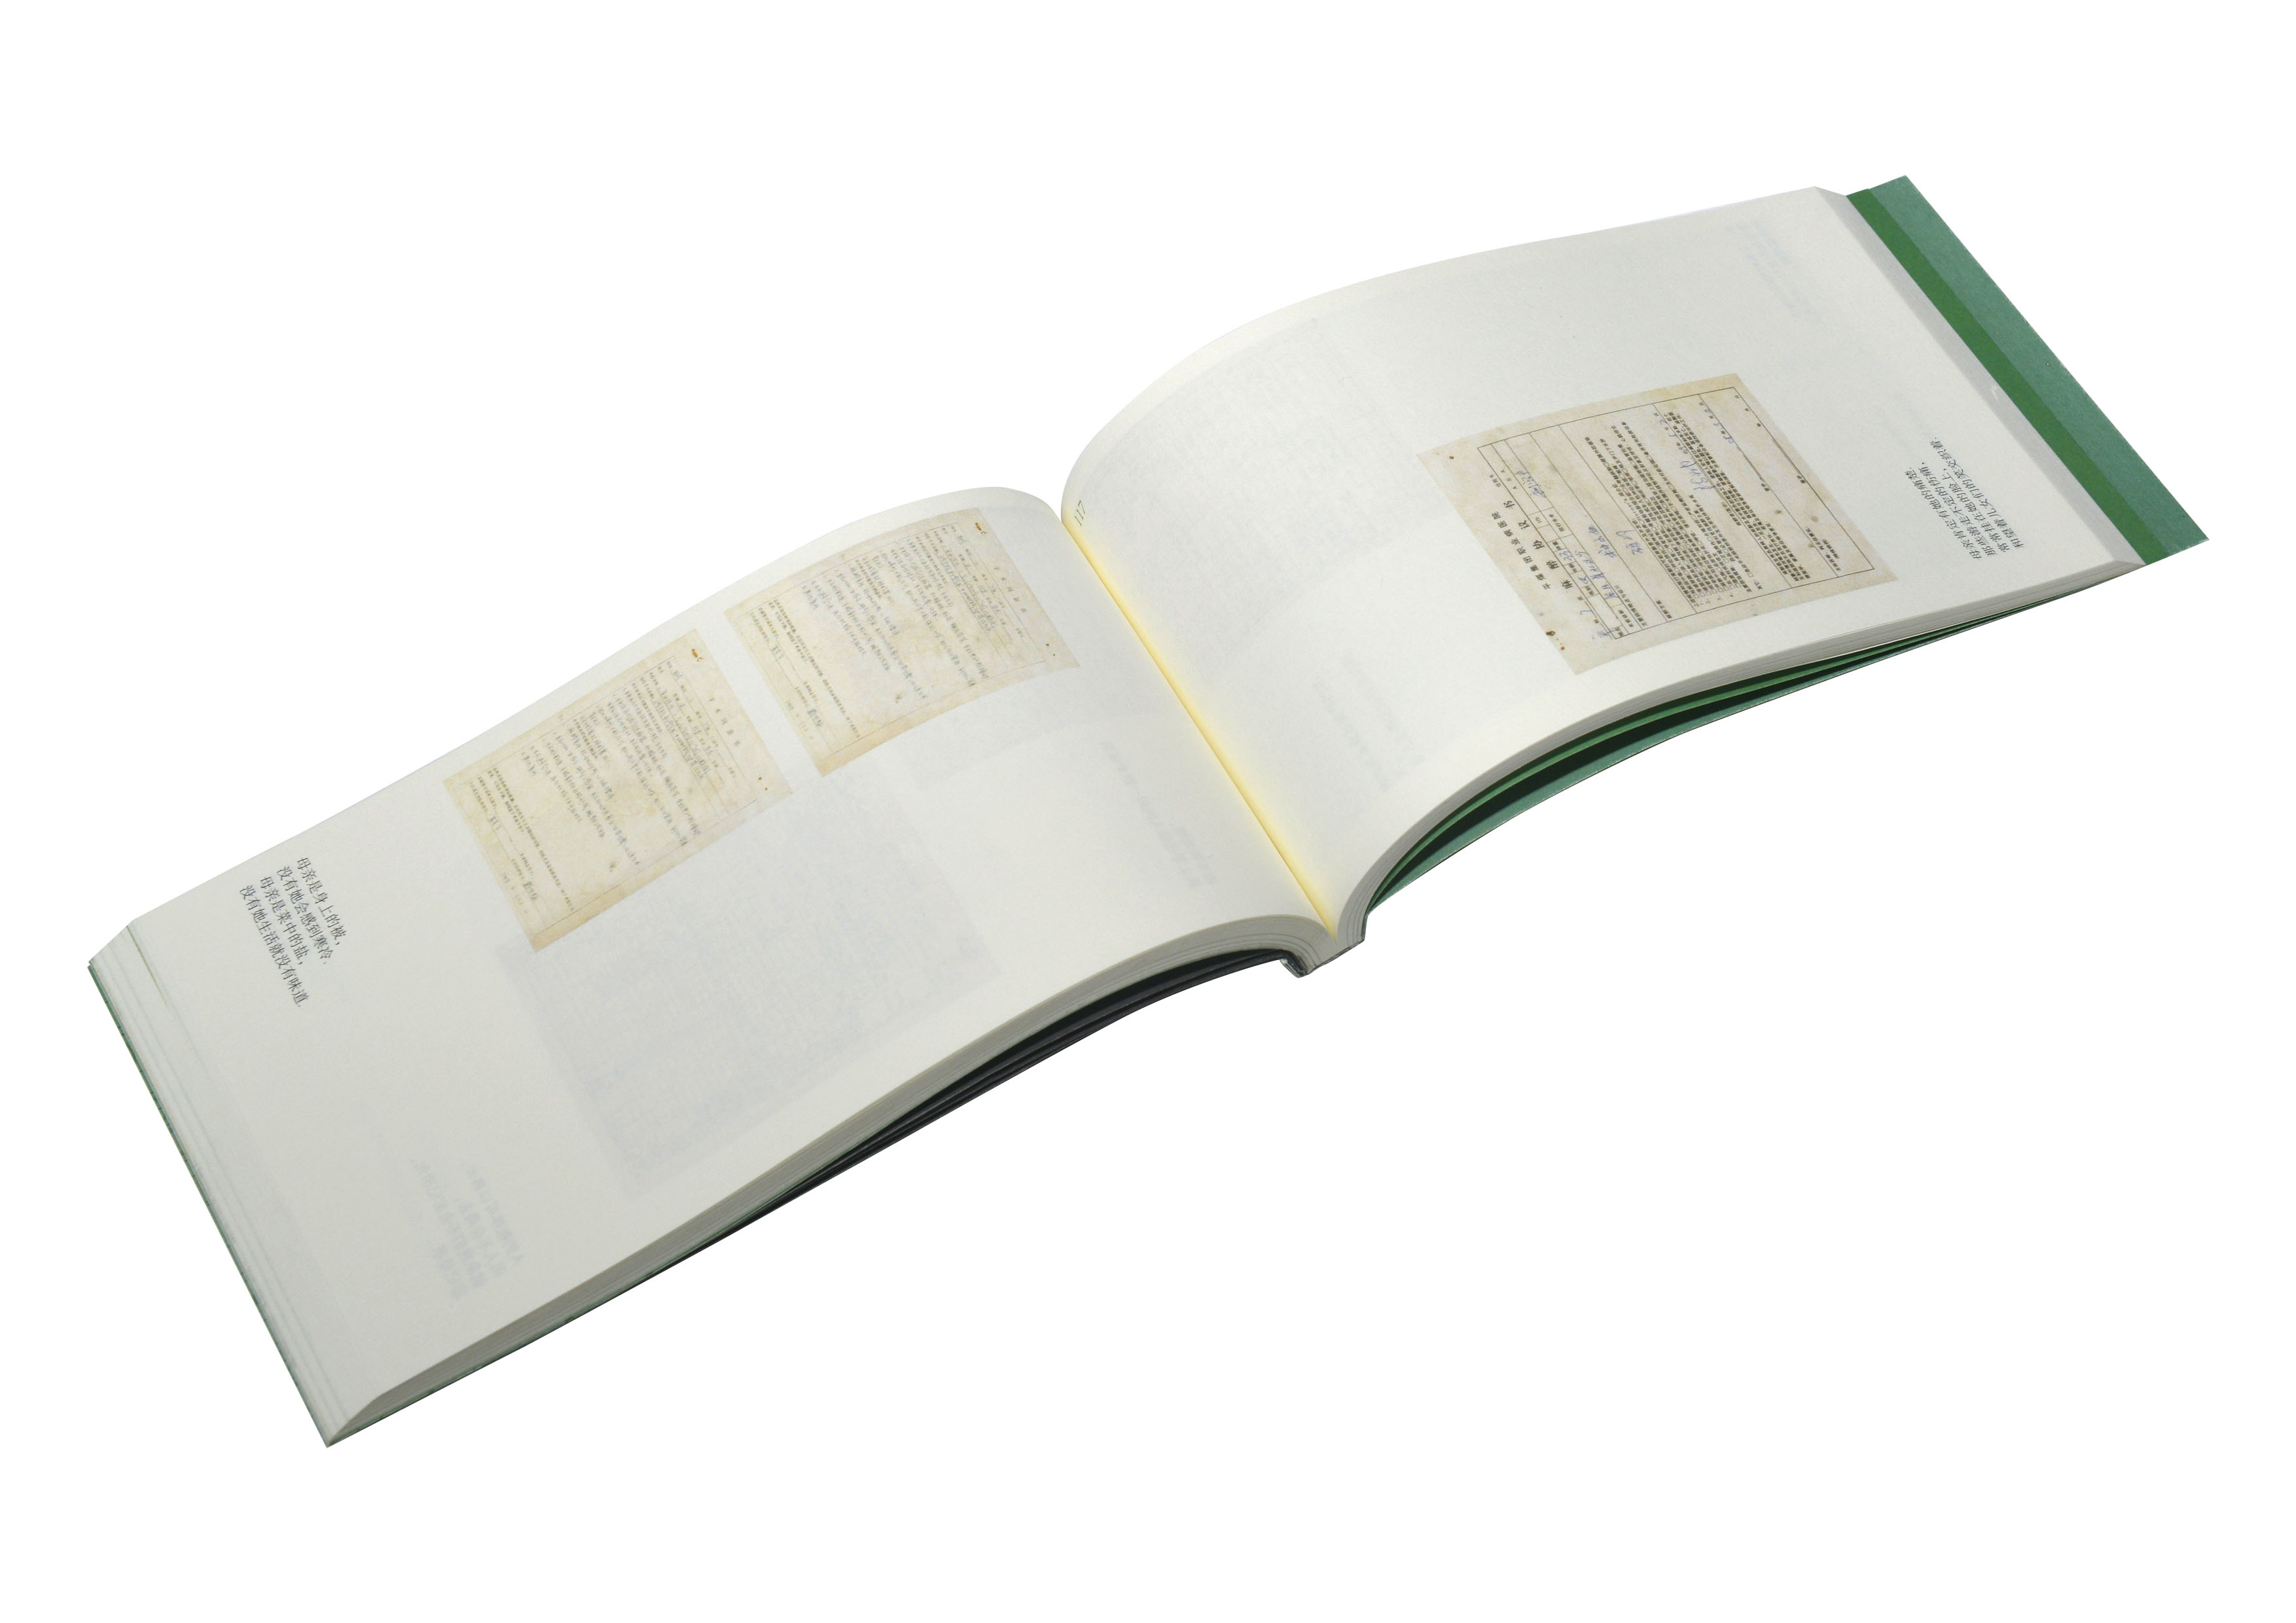

【金獎】

作品名稱:《為母書》

作者姓名:楊迪凱作品分類:書籍設計

指導教師:範珊珊/孫百萌

設計說明:這是一本為作者母親,以及所有要經歷為母者過程的女性所做的書。書中匯集了作者母親數十年行醫過程中的八位孕婦病歷,以及作者母親的行醫感悟,試圖從人文學角度解析母親孕育生命的過程,體現母親在生命孕育過程中所做的努力與艱辛。提取病歷顏色作為主色調,提取病例裝訂方式應用於本書,配合有關詩歌,突出人文關懷。